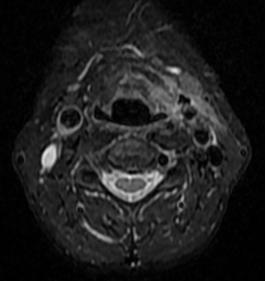

经保守治疗至第3天时,复查电子喉镜及颈部MRI检查后,提示病情无明显改善,并且咽喉会厌脓肿已形成并破溃流脓、颈深部脓肿形成,且范围大,炎症累及上纵膈边缘,脓肿一旦破入胸腔,死亡风险大大增加,病情相当危险,不能再耽搁。

(术前MRI平扫+增强)